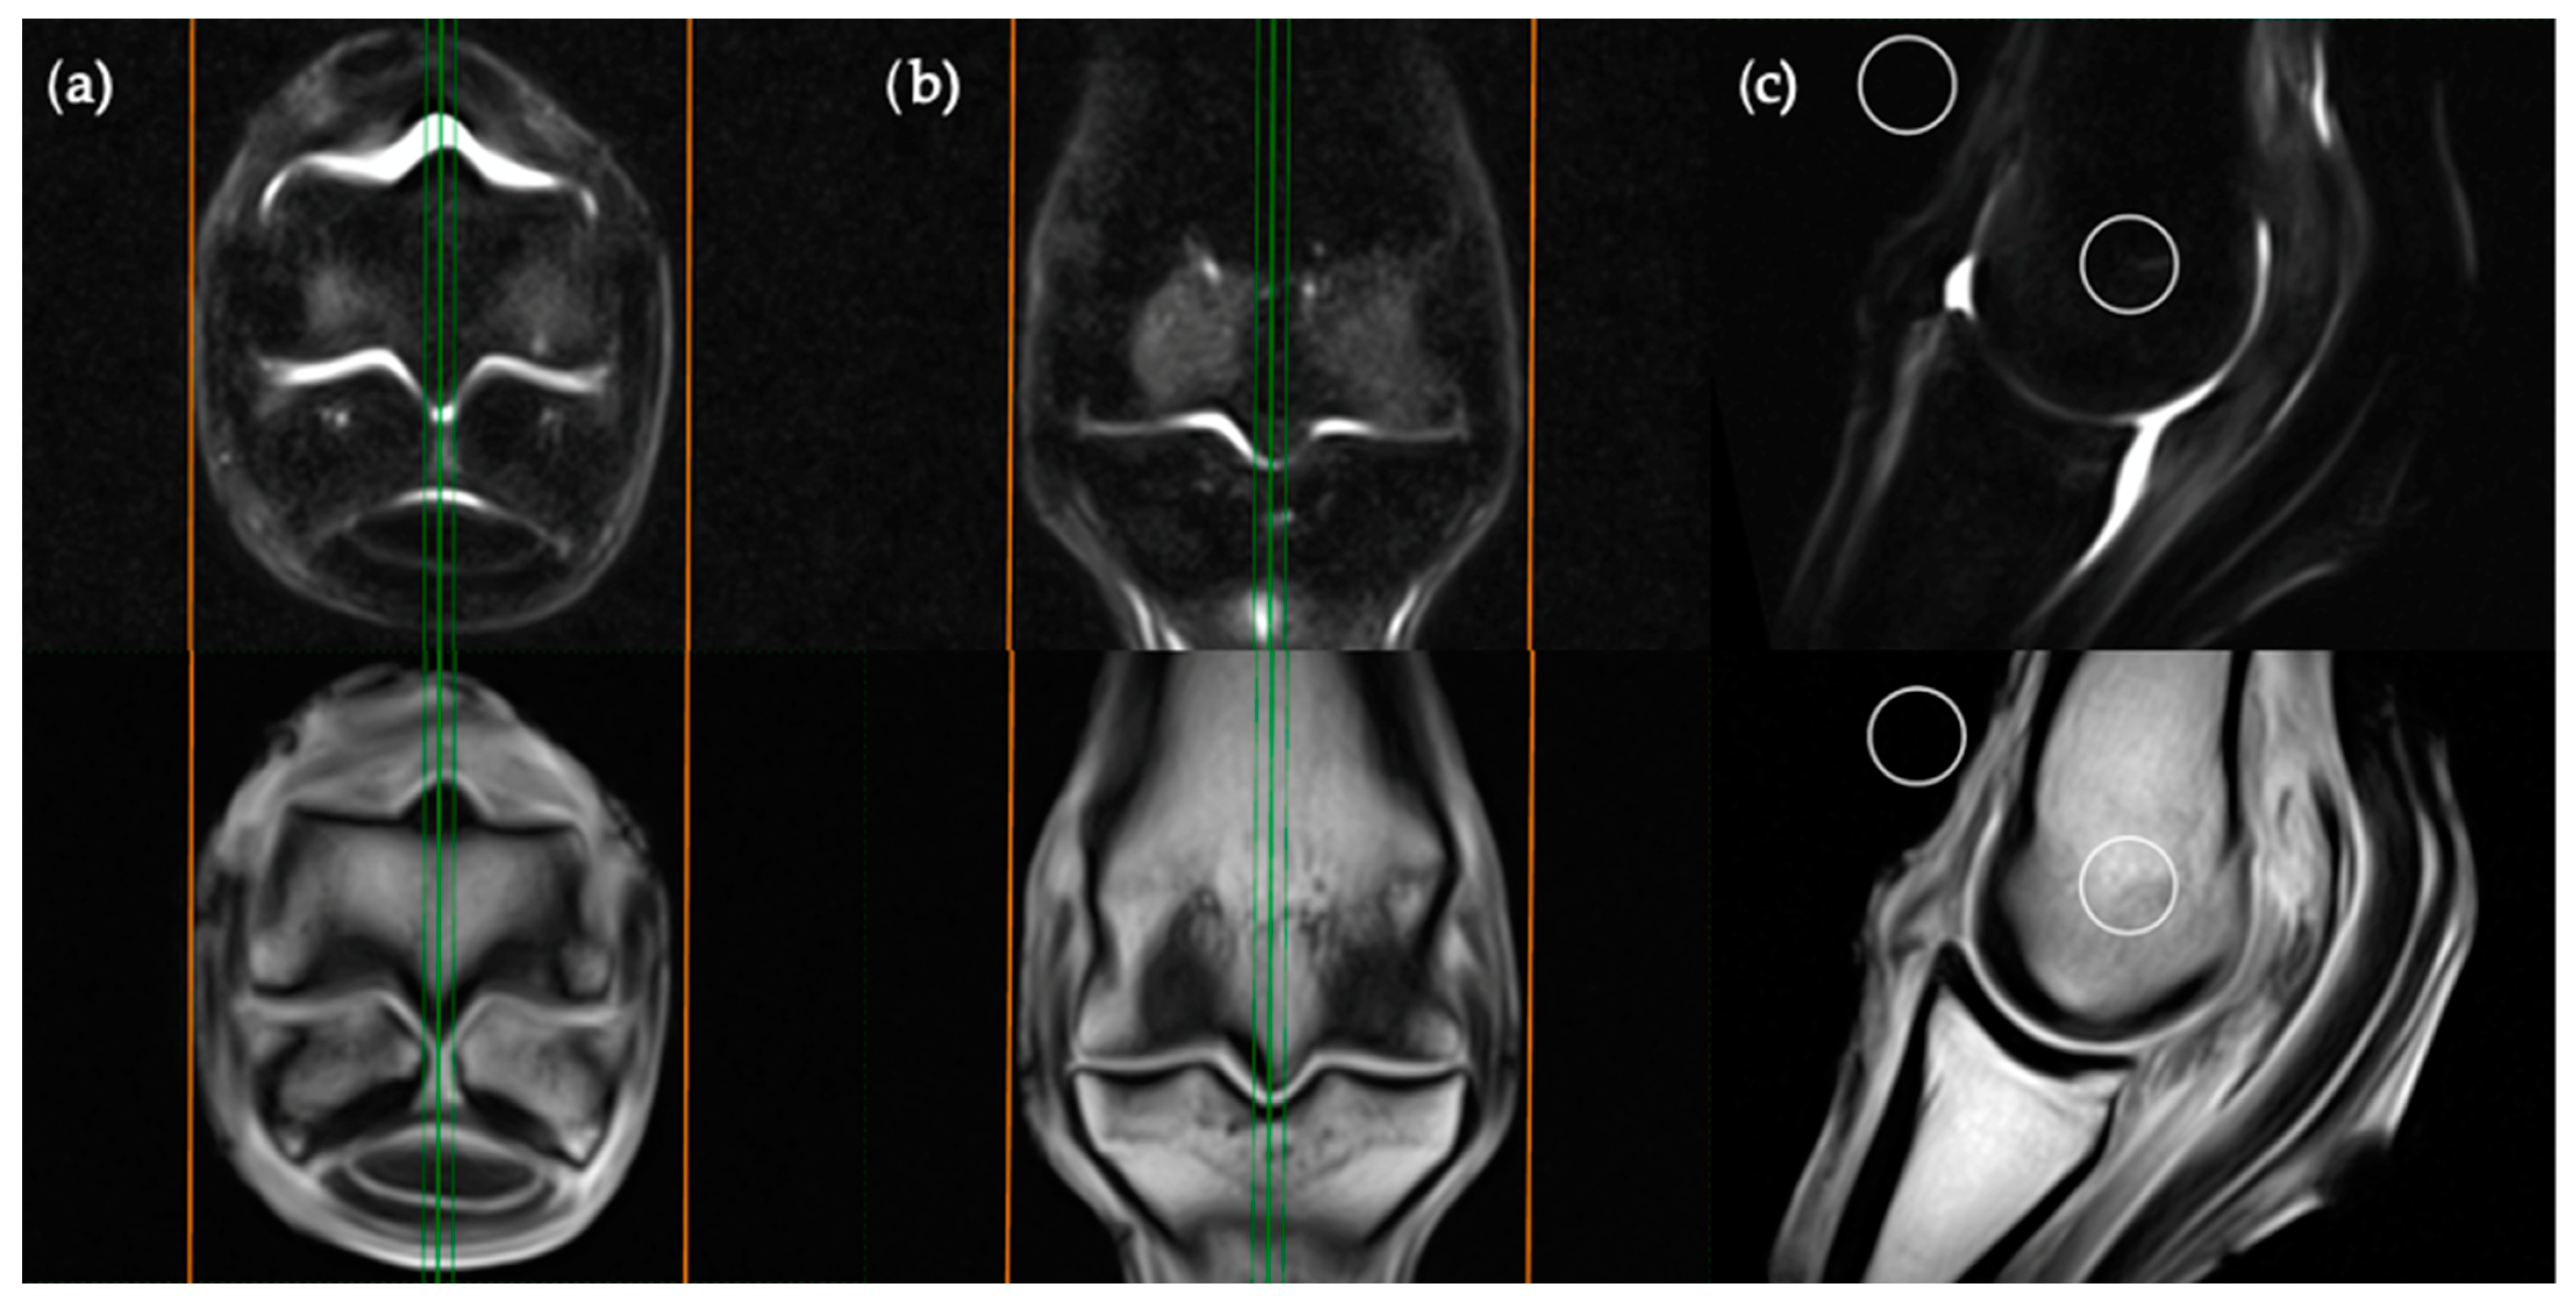

Images were viewed by a veterinary radiologist experienced with the interpretation of low-field equine fetlock MRI examinations (AY). MRI studies were viewed in “digital imaging and communications in medicine” (DICOM) format on an interactive DICOM viewer workstation (Osirix MD). Standardised regions of interest (ROIs) of 2 cm2 were imported into each study. The ROIs were positioned in predetermined locations for each plane of the STIR sequences (Figure 1, Figure 2, Figure 3 and Figure 4) then copied across to the corresponding T1W slice. For every intraosseous ROI measured, a background ROI was also placed external to the anatomy in the same image at a consistent, predetermined location. One to three signal to noise ratios (SNRs) were calculated for each image examined in order to evaluate signal changes between images rather than absolute signal value. SNR is the ratio between the amplitude of the MR signal of a tissue and the standard deviation of the amplitude of the background noise. Use of SNR also allowed for image window and level settings to be adjusted subjectively for each study in order to maximize visualization of intraosseous STIR hyperintensity. Each limb was graded poor, satisfactory, good or excellent for quality of fat suppression in the STIR sequences. The experimental protocol was divided into two parts; blinded and unblinded.

The sagittal plane measurements required three different images for ROI placement; parasagittal slices through the centre of the lateral and medial condyles of the third metacarpal/metatarsal bone (Figure 3) as well as a third image on sagittal midline (Figure 4). In the absence of an image perfectly centred of any of these anatomical locations then the adjacent image containing the greatest amount of STIR hyperintensity was chosen. This was commonly required for the sagittal image ROI. Condylar ROIs were placed at the edge of the subchondral bone plate within the centre of the palmar/plantar half of the lateral and medial condyles. The axial physeal ROI was placed within the axial portion of the bone at the level of the physeal vasculature. The background ROI was placed at the dorsal surface of the limb, proximal to the sagittal ridge of the third metacarpal/metatarsal bone.

Figure 4. STIR FSE (top row) and T1W GRE (bottom row) MRI images in (a) transverse; (b) frontal and (c) sagittal planes; demonstrating the location of axial ROI placement in a sagittal plane. The green lines on the transverse and frontal images show the standardized orientation and location of the sagittal slice for ROI placement. The orange lines show the extent and orientation of all the sagittal slices acquired in the MRI study.